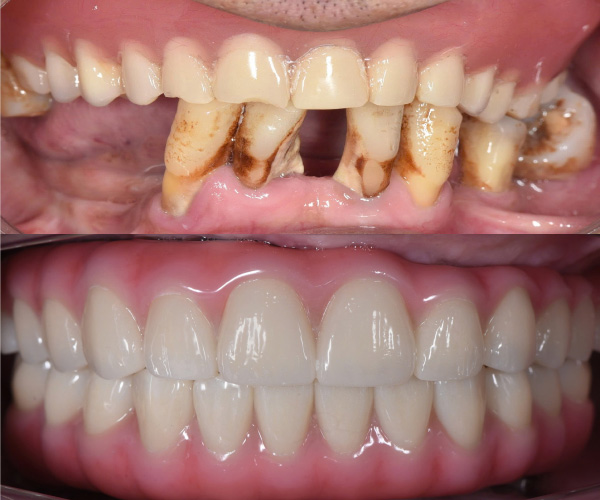

Cấy ghép implant phục hồi toàn diện chức năng nhai và thẩm mỹ cho người bị nha chu nghiêm trọng, người mất răng toàn bộ và người cao tuổi nhiều bệnh nền.

Tiến sĩ, Bác sĩ Võ Văn Nhân với hơn 23 năm kinh nghiệm trong lĩnh vực Implant Nha khoa, đã thực hiện thành công hơn 20.000 ca cấy ghép răng Implant từ đơn giản đến phức tạp. Những thành tựu đặc biệt mà Ts.Bs Võ Văn Nhân đạt được góp phần mang lại nụ cười hạnh phúc, mở ra cơ hội cho rất nhiều trường hợp mất răng, không răng bẩm sinh.

Bệnh nhân L.N.L có xương hàm trên bị tiêu trầm trọng cả theo chiều dọc và chiều ngang, chỉ còn một vài milimet, vùng răng sau xương hàm xuống thấp. Ts.Bs Võ Văn Nhân đã thực hiện kỹ thuật cấy Implant xương gò má. Đây là phương pháp rất khó vì Implant có lộ trình dài, nằm gần các cấu trúc giải phẫu quan trọng như màng xoang hàm, thần kinh dưới ổ mắt, sàn ổ mắt,…